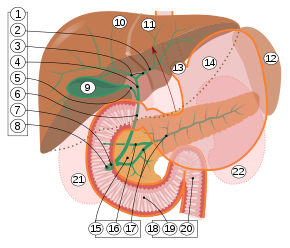

9. Gallenblase, 10–11. Linker und rechter Leberlappen. 12. Milz.

13. Speiseröhre. 14. Magen. 15. Bauchspeicheldrüse: 17. Ductus pancreaticus.

18. Dünndarm: 19. Zwölffingerdarm, 20. Jejunum

21–22: Nieren

Die menschliche Gallenblase ist normalerweise 8 bis 12 cm lang und 4 bis 5 cm breit. Ihre Form wird oft als „birnenförmig“ beschrieben. Die Gallenblase liegt in der Gallenblasengrube (Fossa vesicae biliaris) der Unterseite der Leber zwischen deren Lobus quadratum (quadratischer Lappen) und Lobus dexter (rechter Lappen) an, kann aber auch vom Gewebe der Leber umschlossen sein. Nach kaudal steht das Organ in Beziehung zur Flexura coli dextra, der rechten Biegung des Dickdarms (Colon), was bei Entzündungen zu Verwachsungen zwischen den beiden Organen führen kann, oder auch zu Verbindungen zwischen den jeweiligen Hohlräumen (biliodigestive Fistel). Dorsal (rückenwärts) befindet sich die Gallenblase nach medial in unmittelbarer Nähe der Pars superior des Zwölffingerdarms (Duodenum).[2] Bei den Schlangen liegt die Gallenblase hinter der Leber und relativ weit von dieser entfernt.